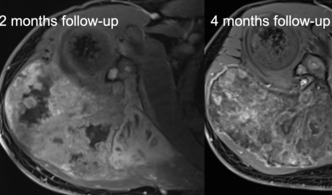

Primäre Knochen- und Weichteiltumore sind seltene, aber potenziell tödliche Pathologien, die mittels MR-Bildgebung diagnostiziert werden. Die Ergebnisse nach Bestrahlung, Chemotherapie und/oder Operation von muskuloskelettalen Tumoren unterscheiden sich je nach Tumorentität, pathologischem Grading, Tumorlage und anderen Parametern. Die MR-Bildgebung liefert nicht nur genaue Informationen über die Tumorlokalisation, die Tumorgröße und die beteiligten und infiltrierten Strukturen, sondern kann auch Differentialdiagnosen eingrenzen, die therapeutischen Auswirkungen überwachen (Abbildung 10) und bei der Nachsorge Lokalrezidive erkennen.